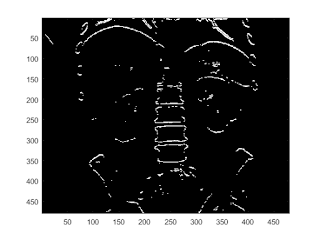

threshold

imagesc(abs(I2)>60);

prewitt edge filter

b = fspecial('prewitt'); I2 = conv2(I,b.','same'); imagesc(abs(I2)); colorbar caxis([0,300])

imagesc(abs(I2)>150)